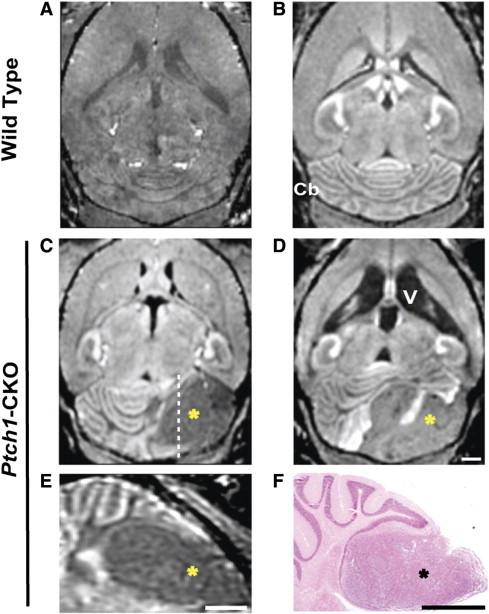

Mouse models have increased our understanding of the pathogenesis of medulloblastoma (MB), the most common malignant pediatric brain tumor that often forms in the cerebellum. A major goal of ongoing research is to better understand the early stages of tumorigenesis and to establish the genetic and environmental changes that underlie MB initiation and growth. However, studies of MB progression in mouse models are difficult due to the heterogeneity of tumor onset times and growth patterns and the lack of clinical symptoms at early stages. Magnetic resonance imaging (MRI) is critical for noninvasive, longitudinal, three-dimensional (3D) brain tumor imaging in the clinic but is limited in resolution and sensitivity for imaging early MBs in mice. In this study, high-resolution (100 μm in 2 hours) and high-throughput (150 μm in 15 minutes) manganese-enhanced MRI (MEMRI) protocols were optimized for early detection and monitoring of MBs in a Patched-1 (Ptch1) conditional knockout (CKO) model. The high tissue contrast obtained with MEMRI revealed detailed cerebellar morphology and enabled detection of MBs over a wide range of stages including pretumoral lesions as early as 2 to 3 weeks postnatal with volumes close to 0.1 mm(3). Furthermore, longitudinal MEMRI allowed noninvasive monitoring of tumors and demonstrated that lesions within and between individuals have different tumorigenic potentials. 3D volumetric studies allowed quantitative analysis of MB tumor morphology and growth rates in individual Ptch1-CKO mice. These results show that MEMRI provides a powerful method for early in vivo detection and longitudinal imaging of MB progression in the mouse brain.